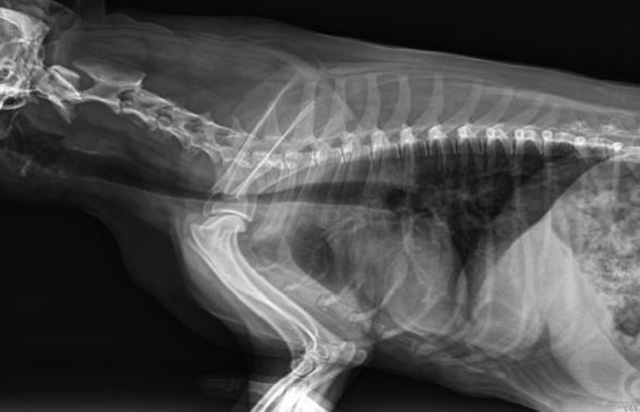

從臨床角度出發(fā),大力發(fā)展動(dòng)態(tài)DR,以精準(zhǔn)的診斷為小動(dòng)物保駕護(hù)航。寵物DR升級(jí)使用雙焦點(diǎn)球管,大尺寸平板探測(cè)器,超高頻逆變高壓發(fā)生器。醫(yī)用纖維板臺(tái)面,防止寵物劃傷。寵物DR整機(jī)小巧實(shí)用,骨略結(jié)構(gòu)和器官位置,分類詳細(xì),運(yùn)算更快,讓拍攝條件更科學(xué),有助于提高診斷的準(zhǔn)確性和效率。安裝移動(dòng)非常方便。低輸入電流設(shè)計(jì),220伏常規(guī)電壓。多品種動(dòng)物程序設(shè)定,滿足各個(gè)臨床需求。成像效果顯著,寵物不能言語(yǔ)表達(dá),導(dǎo)致誤診率居高不下。寵物診療均以經(jīng)驗(yàn)診斷為主的方式,確保最小化輻射降低對(duì)醫(yī)生及動(dòng)物的影響。以滿足精細(xì)化的寵物醫(yī)療需求,成為診斷寵物內(nèi)外科疾病的必備工具。使醫(yī)院更有競(jìng)爭(zhēng)力,為醫(yī)院創(chuàng)收增光添彩。

寵物DR的操作流程是什么呢?第一步首先插上整機(jī)電源,然后按下主機(jī)電源。打開高壓發(fā)生器的電源,工作站主機(jī)電源。等待主機(jī)軟件的自動(dòng)啟動(dòng)。通過軟件登記檢查的寵物信息,選擇寵物檢查拍攝部位。調(diào)節(jié)限速器拍攝區(qū)域。關(guān)閉鉛房門,點(diǎn)擊開始拍攝按鈕。拍攝完成調(diào)整圖像并且輸出。